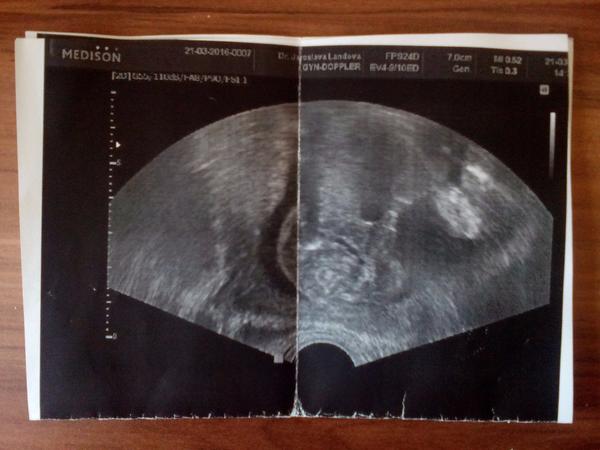

Ahoj maminky a budoucí maminky 😉 Prosím, poradila byste mi některá, co vidíte na fotce z ultrazvuku ve 20. týdnu za pohlaví? Určitě jste foteček viděly už mraky, proto vás žádám o radu...Nechci nikoho ovlivnit, proto svůj tip řeknu později 🙂 Děkuju moc!!!

@pincola jestli je to, co myslím že je, pohlavní hrbolek (ve 14.tt to pinďa ještě není, teda je, ale u holčičky by to vypadalo stejně), tak je miminko kluk-hrbolek směřuje nahoru, nikoli vodorovně "se zádíčky". Tak uvidíš dál 🙂

@inkonginto já nevím, tipla bych spíš holčičku, ale zdá se mi, že miminko neleží úplně na zádíčkách obličejem nahoru, ale je malinko natočené směrem od nás. Tak nevím 🙂

@inkonginto Přijde mi taky špatně natočené, ale můj tip je holčička🙂